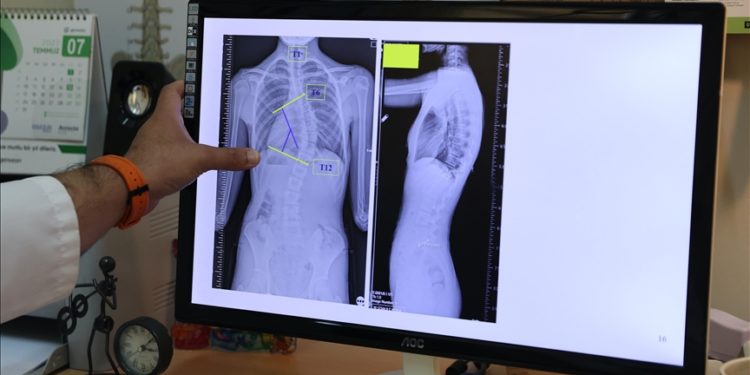

Bakırköy Dr. Sadi Konuk Eğitim ve Araştırma Hastanesi Ortopedi ve Travmatoloji Uzmanı Prof. Dr. Serdar Hakan Başaran, skolyozun yüzde 80’inin ergenlik döneminde ortaya çıktığını belirterek, ergenliğe yaklaşan çocuklarını takip etmeleri için aileleri uyardı.

Başaran, yaptığı yazılı açıklamada, skolyozun omurganın üç boyutlu düzlemde sağa ya da sola eğrilmesi anlamına geldiğini, omurgada S veya C şeklindeki bu eğilmelerin yüzde 80’inin nedeninin bilinmediğini aktardı.

Skolyozun toplumda her 100 kişiden 2-3’ünde ortaya çıktığını kaydeden Başaran, belde ve sırtta ağrılara neden olabilen skolyozun fiziksel görünümü de etkileyebildiğine, daha nadir görülen 80 derecenin üzerindeki eğriliklerin ise akciğer kapasitesini azaltarak hayatı tehdit edebildiğine dikkati çekti.

En sık karşılaşılan skolyoz tipinin ergenlik döneminde görüldüğüne işaret eden Başaran, “Skolyozun çeşitli tipleri var. Serebral palsi gibi hastalıklara ya da doğum travmalarıma bağlı olarak erken bebeklik ya da çocukluk dönemlerinde ortaya çıkabiliyor. Ama en sık karşılaştığımız ergenlikte ortaya çıkan skolyoz tipi. Ergenlikte gördüğümüz skolyoz oranı yüzde 80. Genellikle hafif derecelerde olan skolyoz, çocuğun hızlı büyüme dönemine girdiği bu dönemde hızlı bir şekilde artıyor.” bilgisini paylaştı.

“Toplumda 10 dereceye kadar olan omurga eğriliklerine çok sık rastlıyoruz. Bunları normal, postürel eğrilikler olarak tanımlıyoruz. 10 dereceyi geçen eğriliklerde skolyoz hastalığı tanısı koyuyoruz. 20 dereceye kadar olan eğrilikleri 6 aylık aralıklarla büyüme dönemlerine göre takip ediyoruz. 20 dereceyi geçen eğriliklerde ise çocukları egzersiz programına alıyoruz ya da çeşitli korselerle hastalığının ilerlemesini engellemeye çalışıyoruz.”

Çocukların hızlı büyüdüğü dönemde önerdikleri korse ve egzersizin, aslında skolyozu iyileştirmeye yönelik tedaviler olmadığını, burada cerrahi sınıra yaklaşmadan hastalığı durdurabilmeyi amaçladıklarını ifade eden Başaran, erişkinlik döneminde 40 dereceyi aşan omurga eğriliğinde cerrahi tedavi önerdiklerini aktardı.

Skolyozun erken tanısının önemini vurgulayan Başaran, ailelere seslenerek, “Ergenliğe yaklaşan çocuklar skolyoz açısından ailenin takibinde olmalı. Omuzlarında, kürek kemiklerinde asimetri ya da sırtında kamburluk olup olmadığına bakabilirler. Çünkü erken dönemde yakalayabildiğimiz skolyozu durdurmaya çalışıyoruz.” ifadesini kullandı.